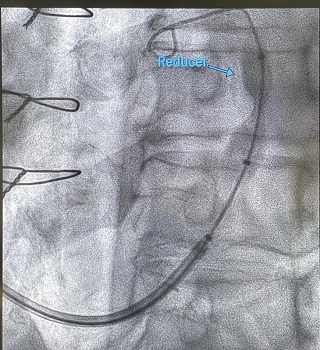

Il sistema Neovasc Reducer™ è destinato a pazienti selezionati e spesso definiti “no option”, ovvero che presentano angina pectoris refrattaria associata a provata ischemia miocardica reversibile, con limitate opzioni di trattamento. “L’impianto – spiega la Dott.ssa Truffa – viene eseguito a paziente sveglio; il dispositivo viene introdotto nel seno coronarico (una vena del cuore) attraverso un accesso venoso giugulare destro o sinistro, in anestesia locale. Il corretto posizionamento viene identificato sotto guida fluoroscopica (raggi X). A quel punto si gonfia il pallone su cui il sistema a forma di “clessidra” è montato per essere posizionato correttamente in una parte del vaso.” Tra i casi trattati ad Asti, si registrano situazioni ormai croniche e fortemente invalidanti, tra cui quella di una paziente che soffriva di questo disturbo da circa 15 anni. Già quattro i pazienti impiantati negli ultimi mesi, tutti fortemente sintomatici per angina nonostante una piena terapia farmacologica, con test d’ischemia positivo, due dei quali già sottoposti a precedenti by-pass e rivascolarizzazioni multiple, non più “aggredibili” dal punto di vista né chirurgico né percutaneo. A seguito di questi interventi, tutti i pazienti hanno avuto un miglioramento della qualità di vita (già dopo il primo mese dall’impianto) con scomparsa pressoché totale dei sintomi anginosi, miglioramento della tolleranza allo sforzo e riduzione della terapia farmacologica assunta.